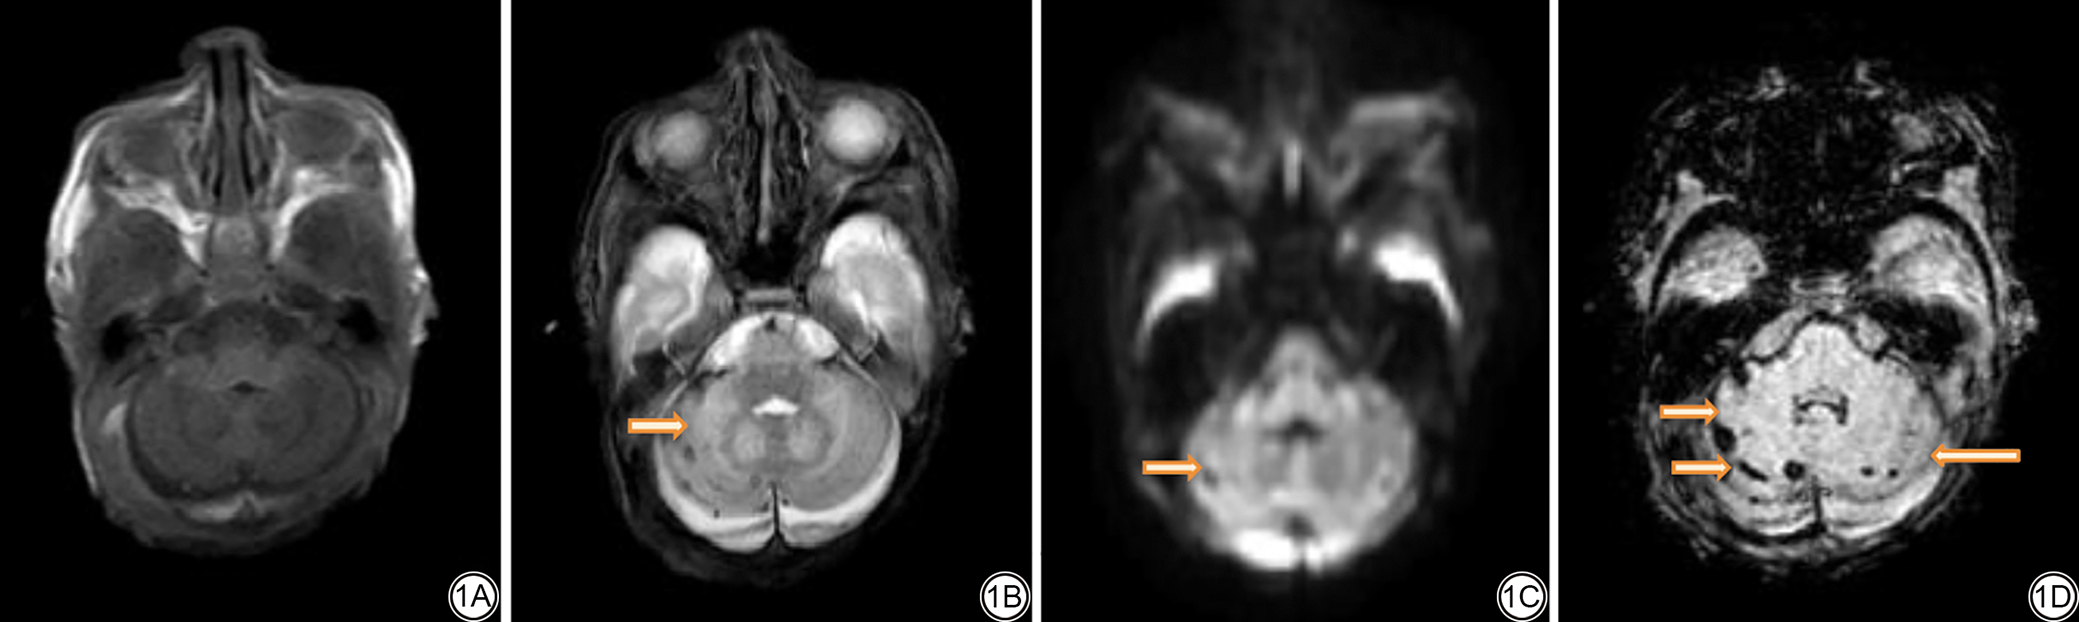

图3  女,胎龄35+2周,早产。3A示右侧侧脑室旁短T1WI高信号影,3B示右侧侧脑室旁短T2WI低信号影,3C示双侧侧脑室旁DWI可见高信号影,3D示对应区域SWI等信号。提示该病灶为缺血性脑白质损伤,不含出血。T1WI:T1加权成像;T2WI:T2加权成像;DWI:扩散加权成像;SWI:磁敏感加权成像。

Fig. 3  Scans of a premature female (gestational age = 35+2 weeks). 3A: The right paraventricular area exhibited a high T1WI signal shadow; 3B: The right paraventricular area exhibited a low T2WI signal shadow; 3C: DWI of the bilateral paraventricular area showing a high signal shadow; 3D: The corresponding region on SWI, showing other signals suggestive of ischemic white matter lesion without bleeding. T1WI: T1-weighted images; T2WI: T2-weighted images; DWI: diffusion-weighted imaging; SWI: susceptibility-weighted imaging.